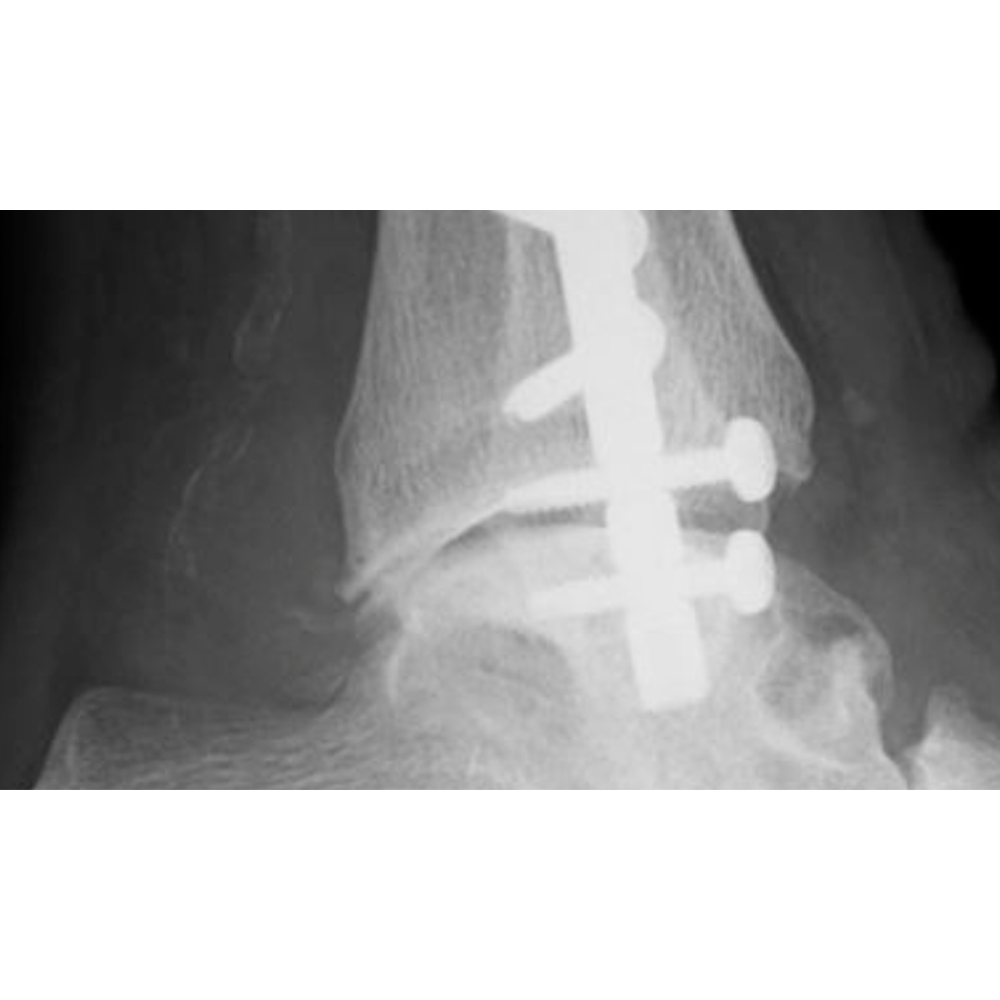

Voorbeelden van gebruik

Postoperatieve Postoperatieve